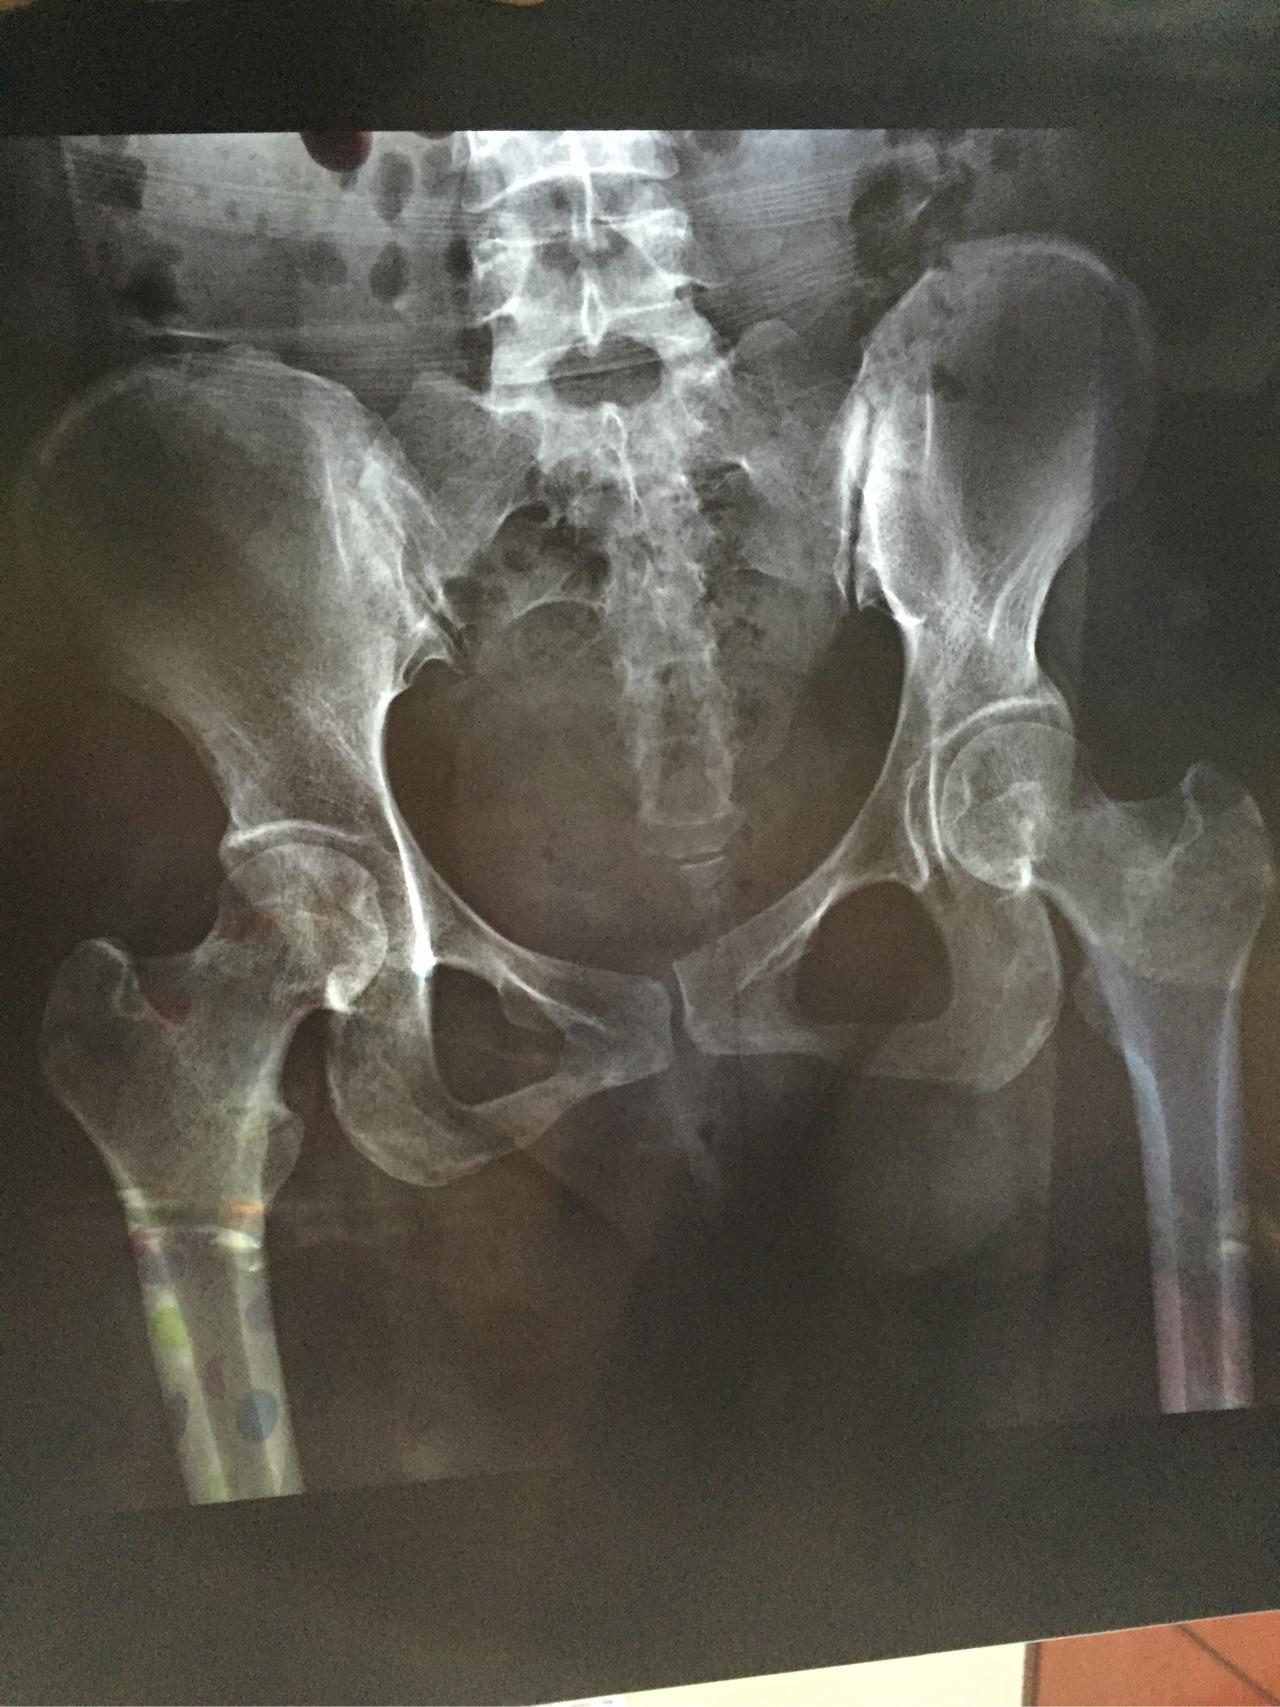

双侧髂骨致密性骨炎有没有好的办法治疗?

图片尺寸1080x1320